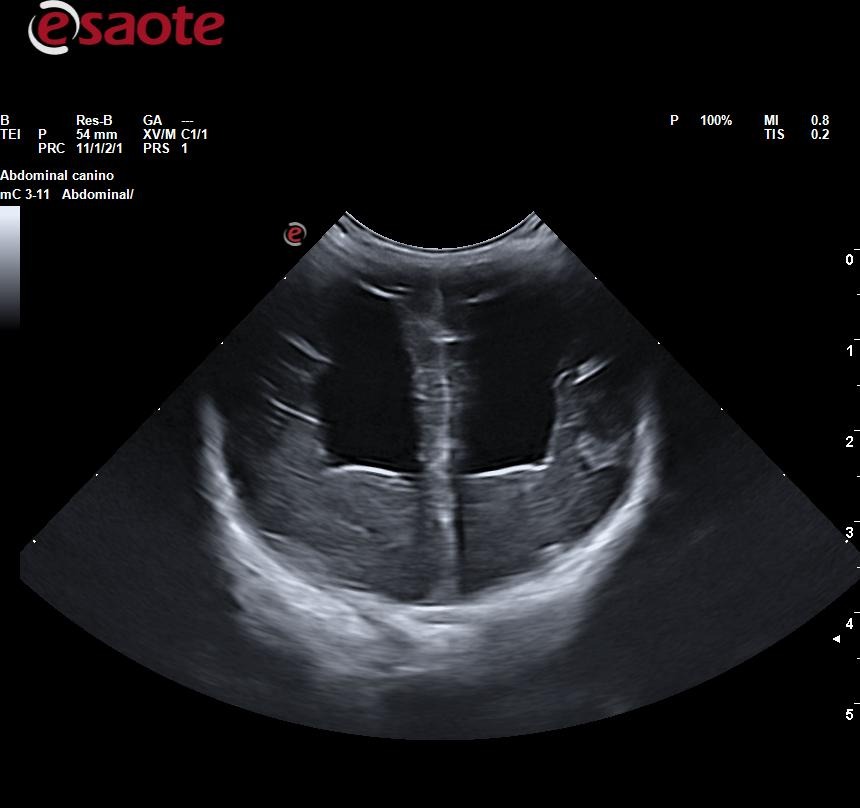

Sienna padece hidrocefalia, una condición muy delicada que pone en riesgo su vida. Fue vendida por un criador y, poco después, sus anteriores tutores nos la trajeron en medio de una crisis convulsiva muy grave. Además, como consecuencia de esas convulsiones, desarrolló una neumonía por aspiración severa que actualmente estamos tratando en la clínica donde trabajo.